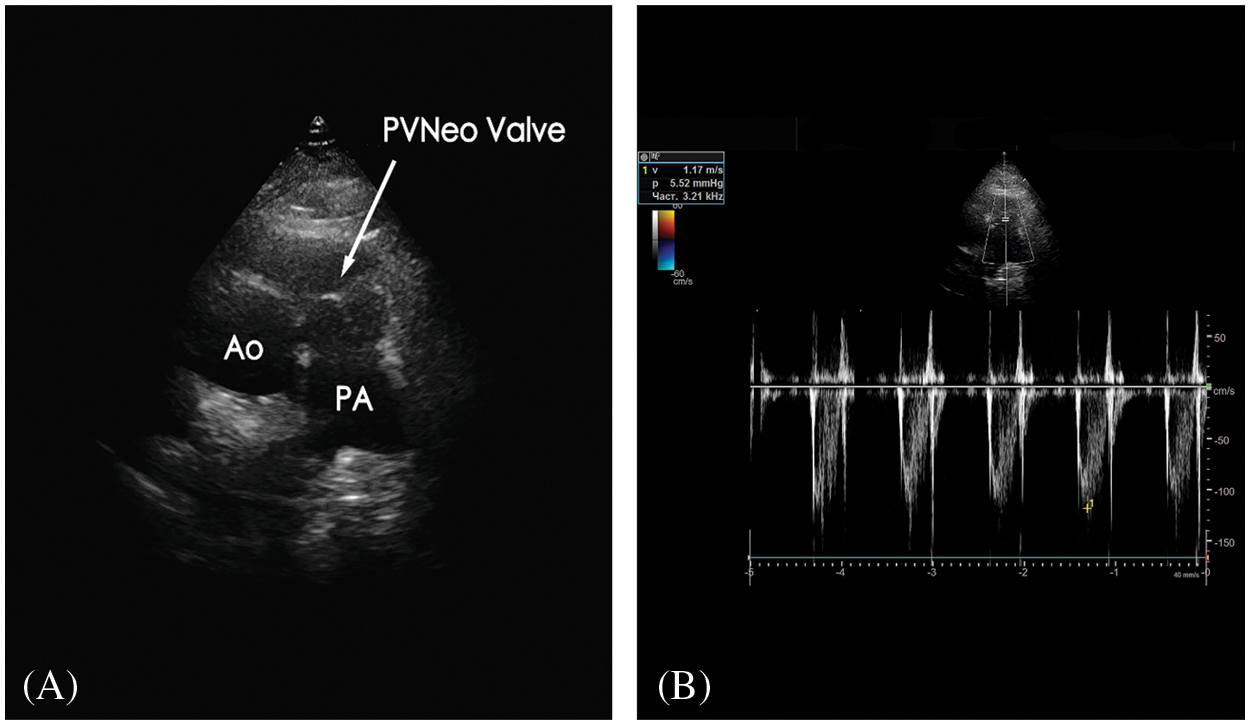

The postoperative period was uneventful. Histopathology of the material from the PV demonstrated old vegetation with zones of fibrinous debris, organizing fibrosis, and chronic inflammation. It did not show any bacterial growth upon evaluation. The patient was discharged on the 9th postoperative day. At the 3-months follow-up, he is in good condition. No clinical and laboratory evidence of relapse endocarditis. On TTE: no residual VSD; PA pressure 37 mm Hg; PVNeo valve is symmetric, with a pressure gradient of 5 mm Hg and trace insufficiency (Figs. 3A and 3B). The patient was given warfarin for one month postoperatively to prevent PVNeo valve thrombosis. Then he was left on low-dose aspirin for six months.

Figure 3: A) Transthoracic echocardiography (modified short-axis view) presents good geometry and function of the reconstructed pulmonary valve. B) Doppler image demonstrates excellent hemodynamic performance of the PVNeo valve at three-month follow-up Ao, aorta; PA, pulmonary artery; PVNeo, pulmonary valve neocuspidization